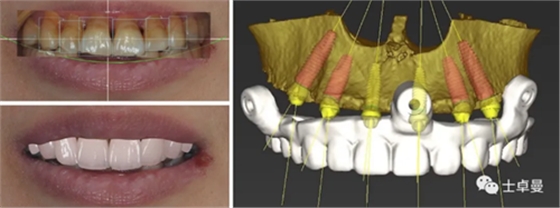

治療計劃

在前述術(shù)前評估的基礎(chǔ)上制定詳細的治療計劃;

通過面部和口內(nèi)相的重疊進行數(shù)字化微笑設(shè)計,以此指導虛擬排牙;

最后根據(jù)排牙信息和頜骨的骨量確定種植體的位置和型號。

a6.png